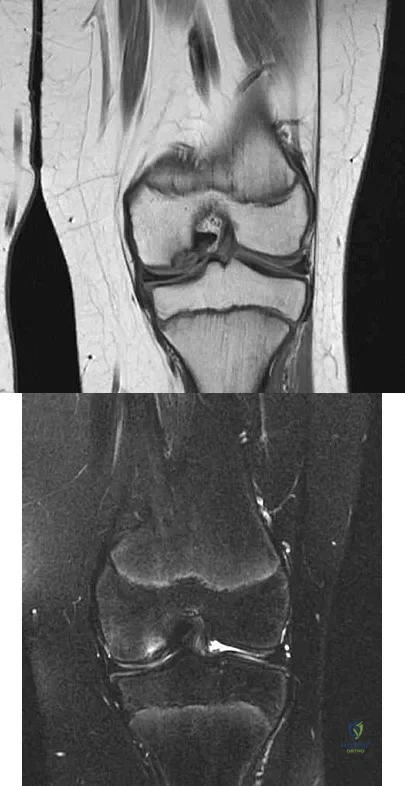

Question 53High Yield

A 74-year-old woman has had acute medial right knee pain for the past 3 months. She denies any history of trauma or previous problems. Coronal and sagittal MRI scans are shown in Figures 11a and 11b. What is the most likely diagnosis?

Explanation